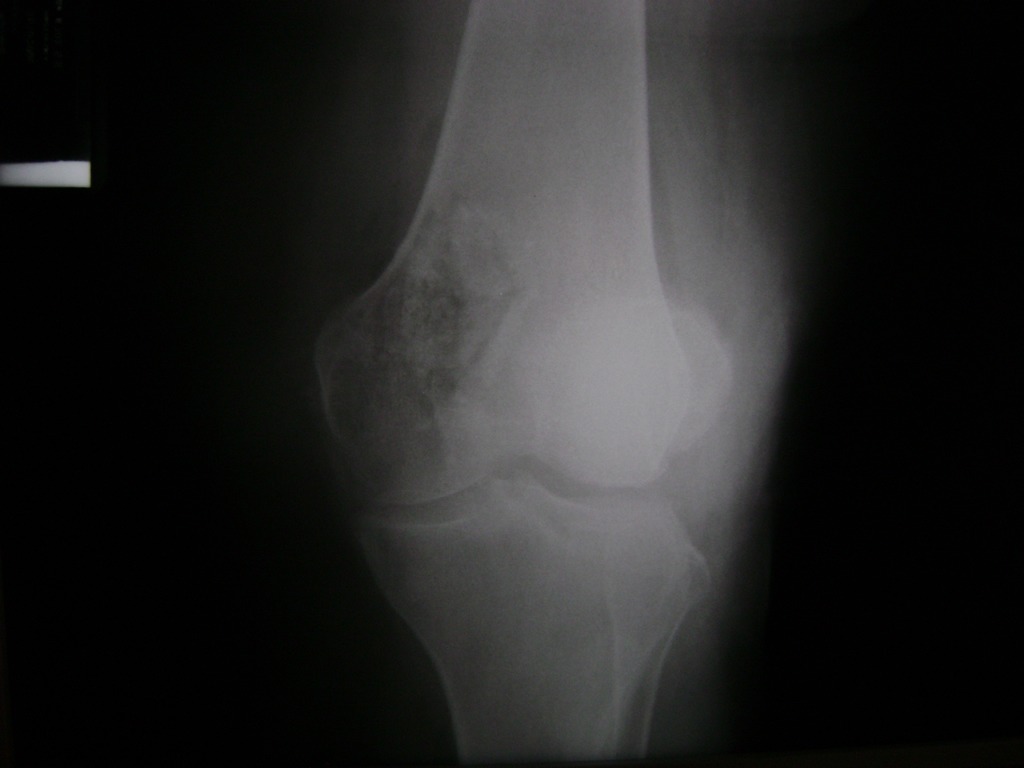

Cirugías de Húmero - Rodilla

La artroscopia de rodilla es un cirugía en el cual la estructura interna de la articulación es examinada ya sea para realizar un diagnostico o para realizar un tratamiento, este procedimiento se realiza utilizando un instrumento parecido a un pequeño tubo llamado artroscopio.